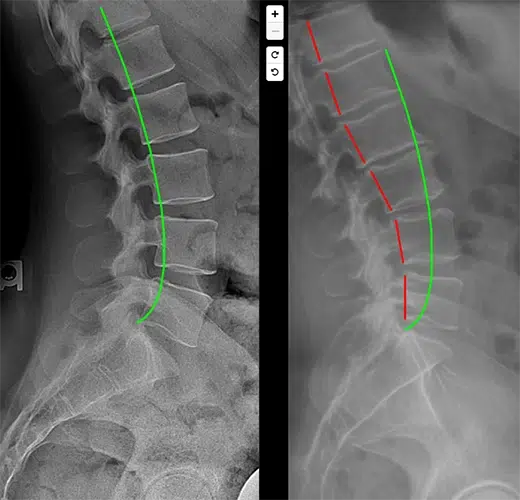

CBP is the most published and peer-reviewed structural corrective technique. By utilizing Mirror Image® adjusting and traction, we work to restore the spine’s natural curvature, taking the mechanical pressure off the disc.

Research Insight: Studies published in Journal of Physical Therapy Science and Archives of Rehabilitation Research show that restoring sagittal spinal alignment (the curve) significantly reduces disc stress and prevents further degeneration compared to traditional therapy.

Step 1: The Structural Analysis. We use digital X-rays and structural testing to see exactly where the disc pressure is coming from.